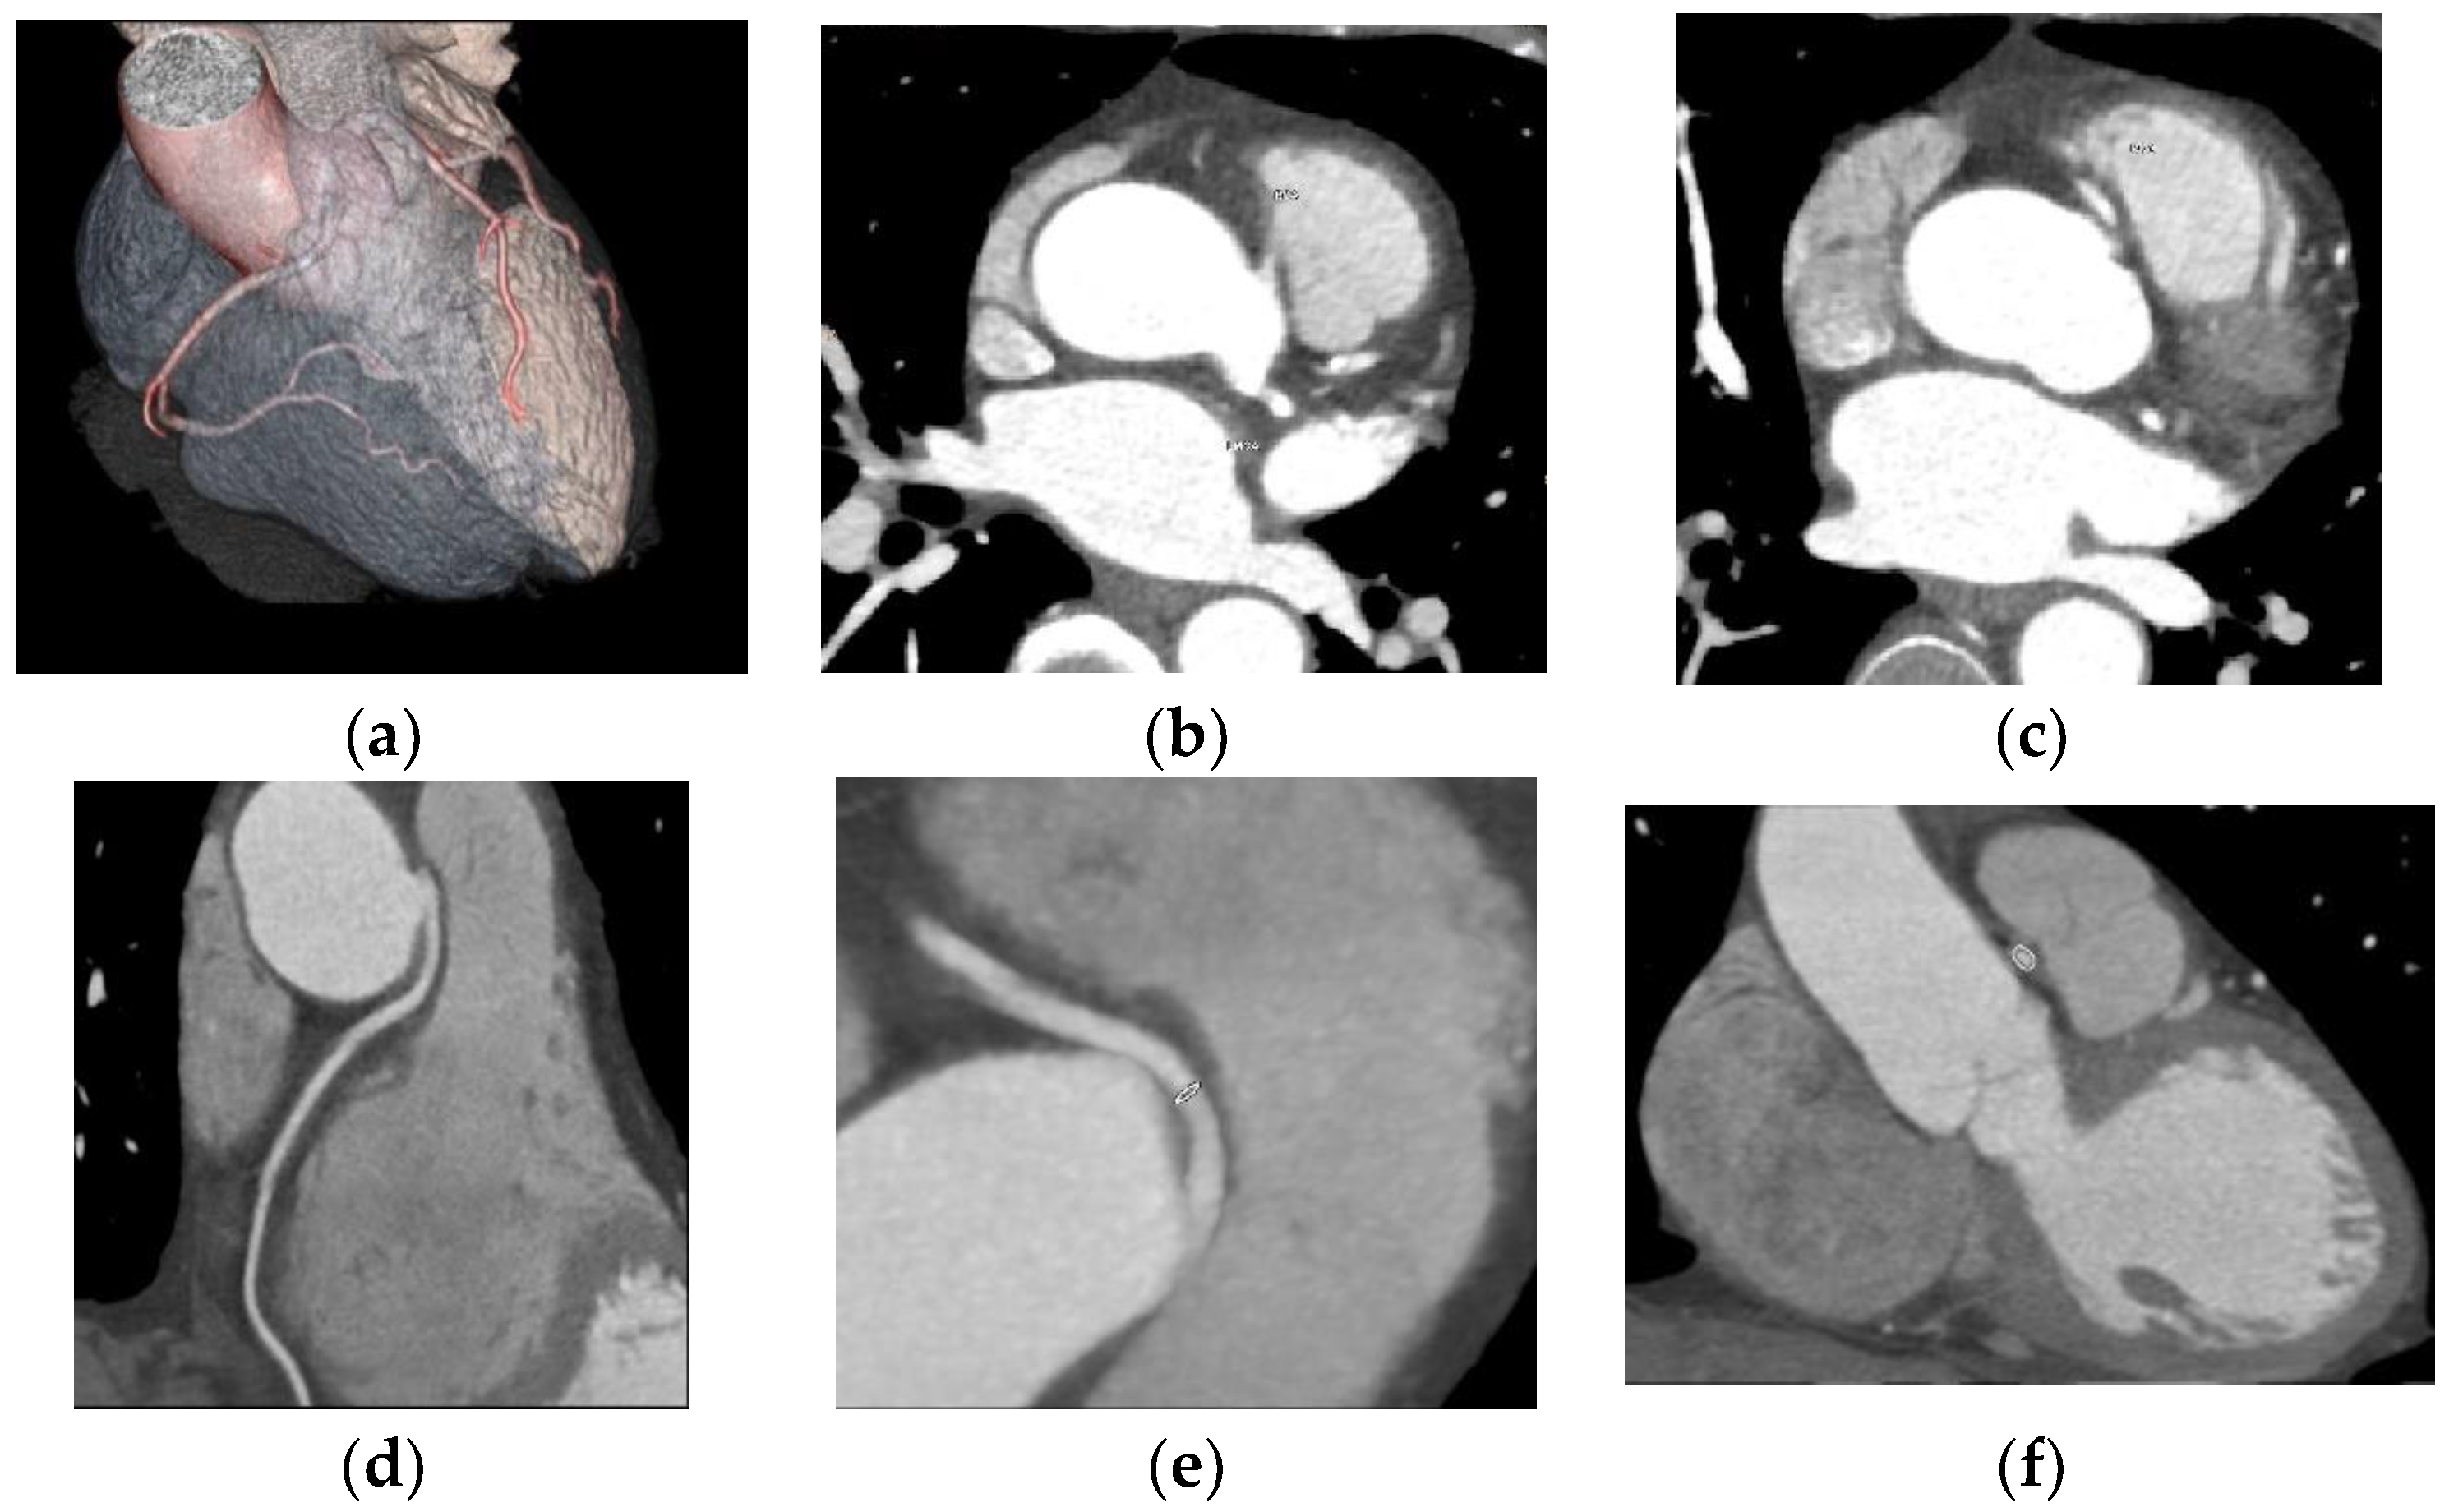

One case of right coronary anomaly originating from the left coronary sinus was found, with an anomalous course between the left pulmonary artery and the aorta, according to

Figure 2.

One case of CAA with a right coronary anomaly originating from the left coronary sinus and an anomalous course between the pulmonary artery and the aorta was detected; a dynamic compressive effect could not be excluded at this level. According to the anatomical classification of the CAA of Angelini, there are several possible routes for the anomalous location of the coronary ostium at improper aortic sinus: in the posterior atrioventricular groove, retroaortic, between the aorta and the pulmonary artery, intraseptal, anterior to the pulmonary flow, in the posteroanterior interventricular groove [

8]. The CAA with a route between the aorta and the pulmonary artery is considered the highest-risk route and is associated with an increased risk of sudden death. Young people are the most vulnerable to sudden death; the risk decreases for middle-aged and elderly people [

5,

21,

22]. One hypothesis for why this effect occurs is that, during exercise, the aortic root and the pulmonary trunk expand and compress the coronary that passes between them. Another hypothesis is that the course of the coronary artery is partially embedded in the aortic wall and is laterally compressed during exertion [

5,

22,

23].